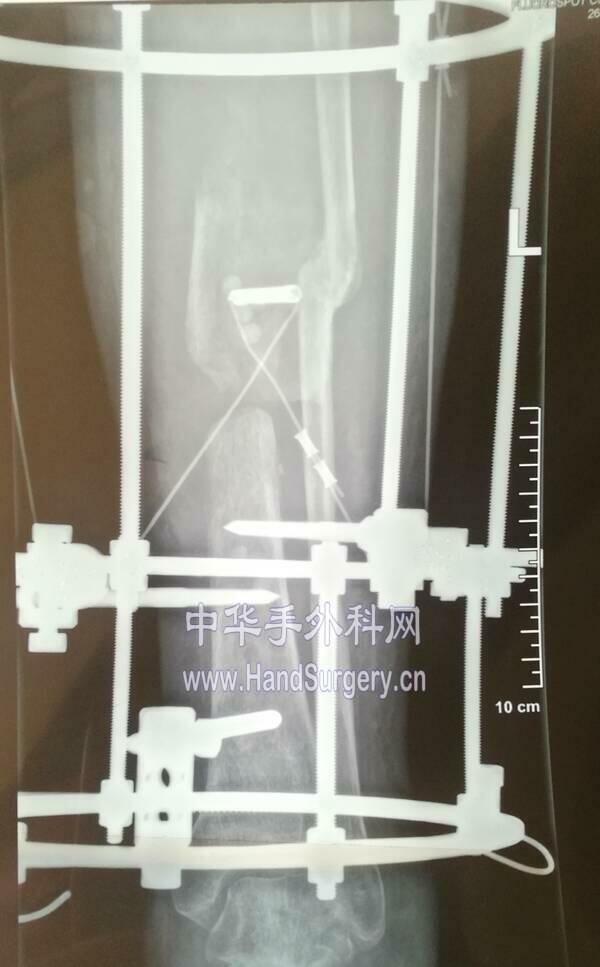

单边外架双段截骨骨搬运

IMG_20190318_200814.jpg

IMG_20190318_123403.jpg

IMG_20190319_103709.jpg

术后跨关节铰链式外架支撑

IMG_20190318_200917.jpg